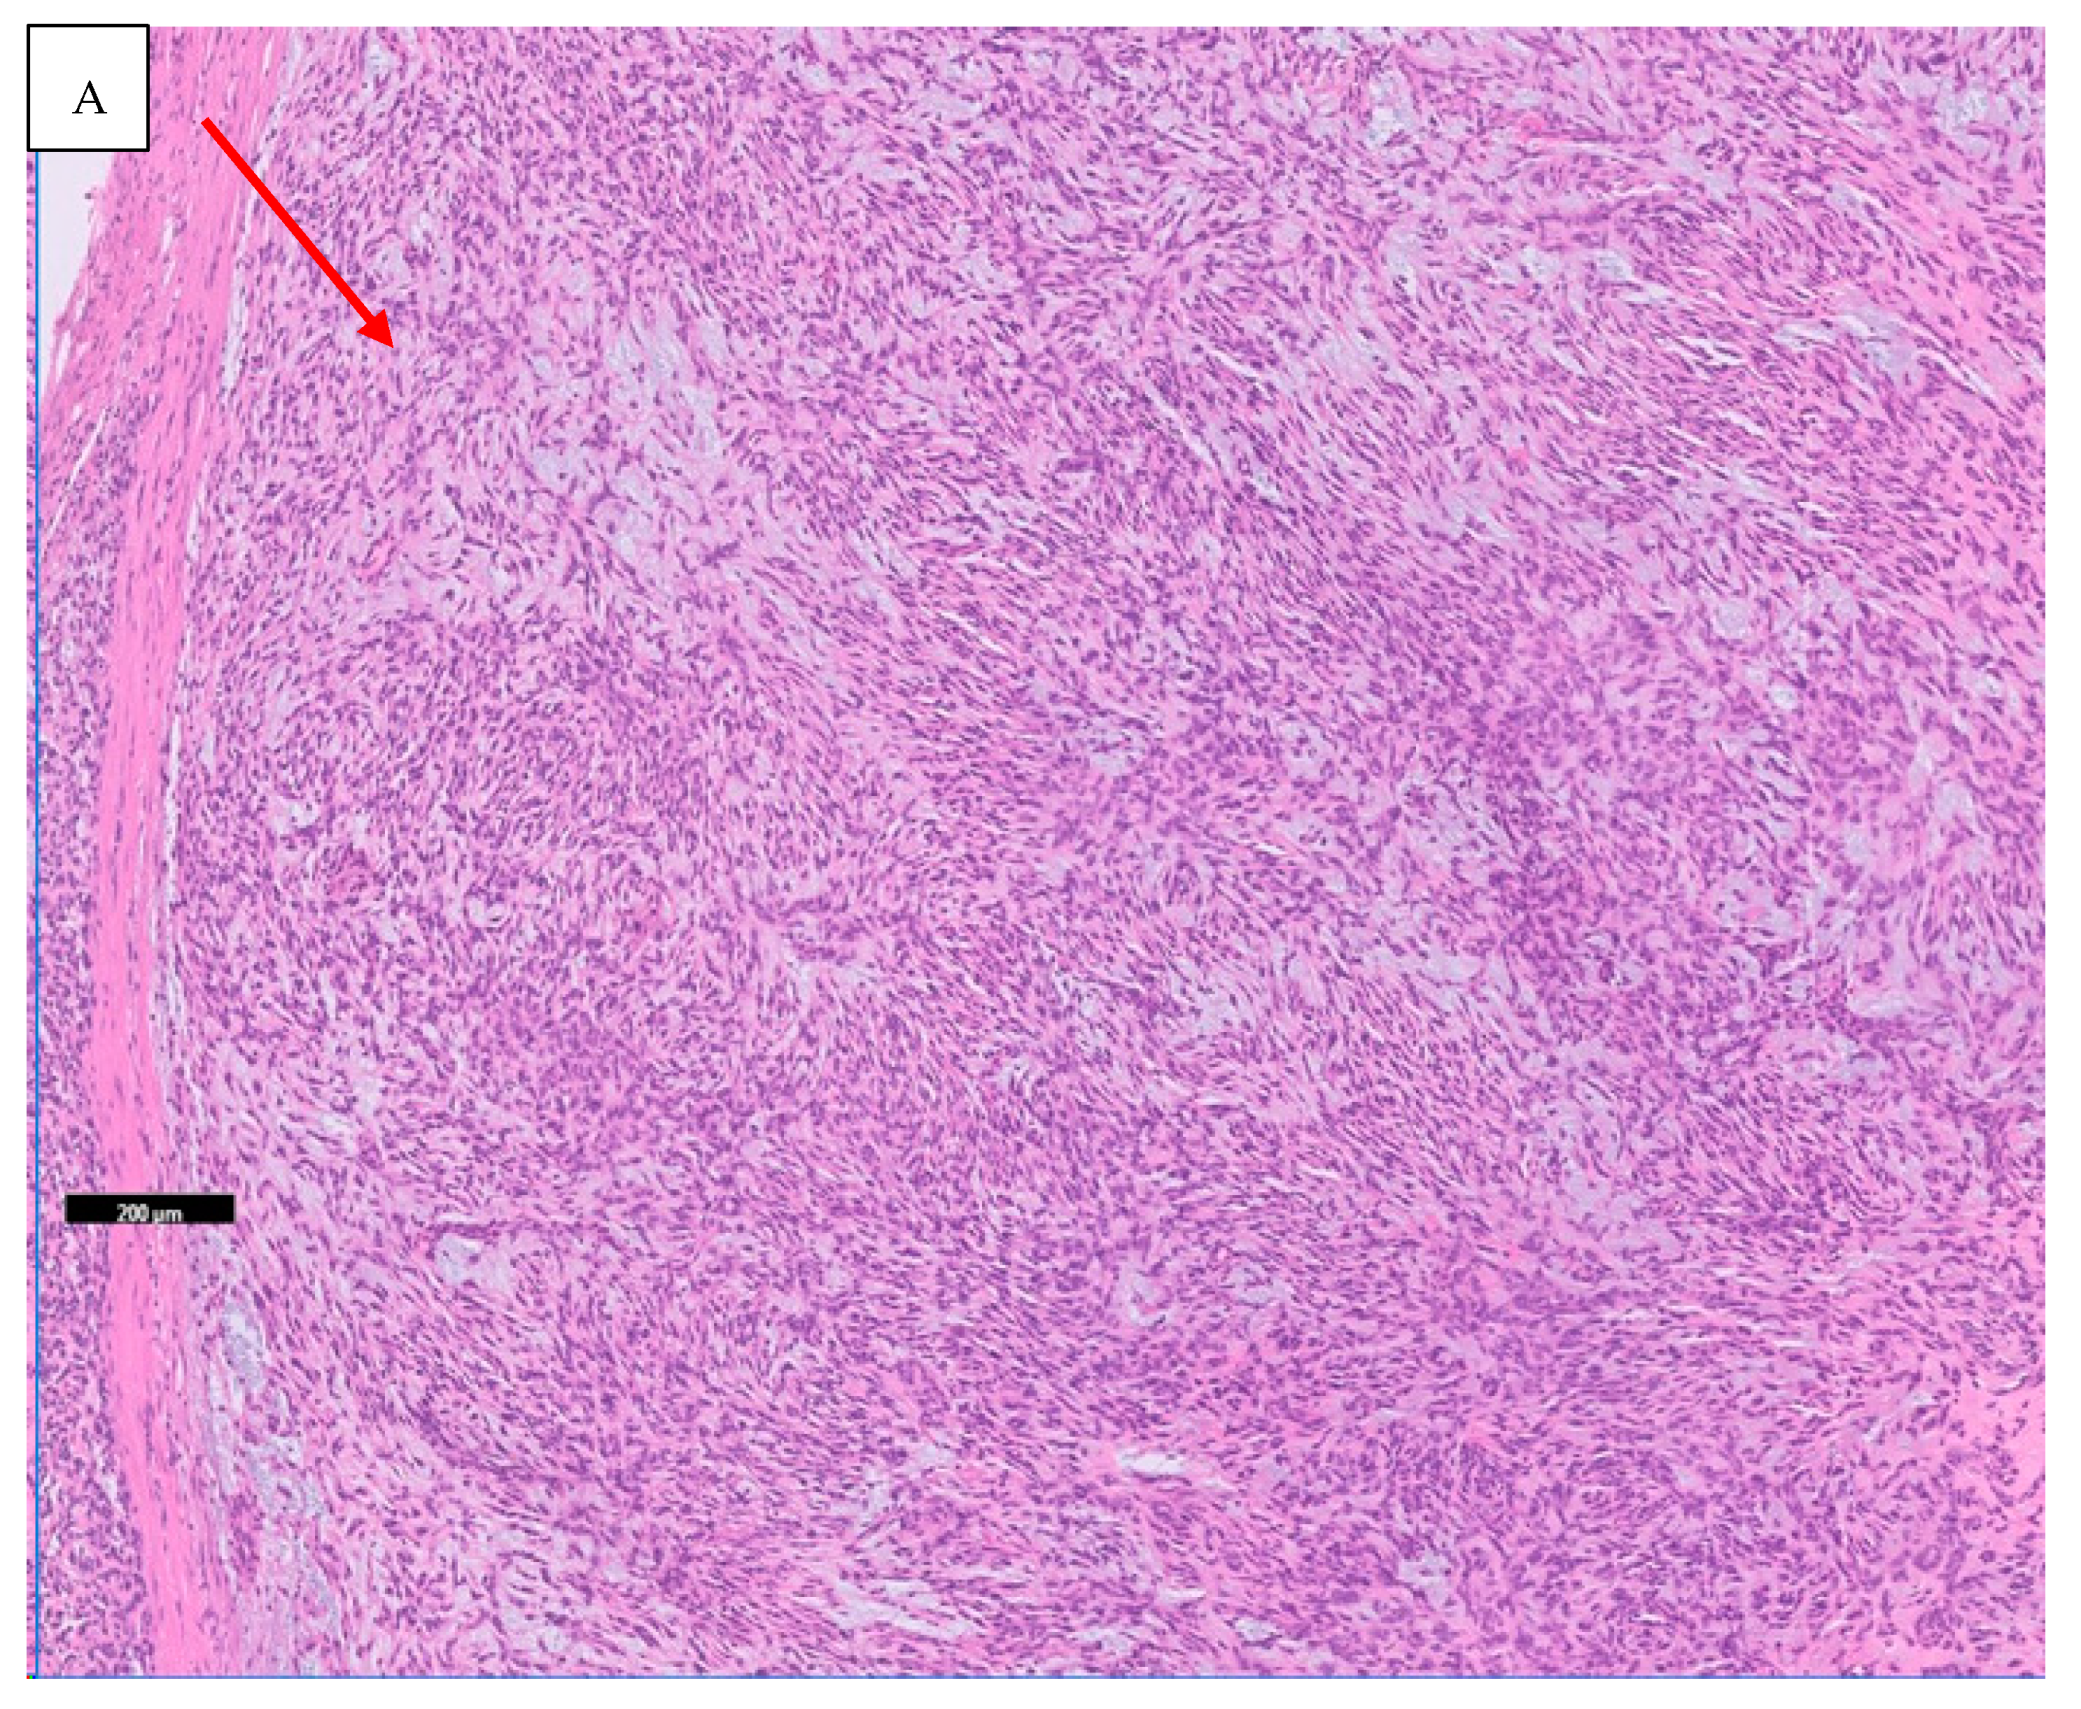

- Haller, F.; Knopf, J.; Ackermann, A.; Bieg, M.; Kleinheinz, K.; Schlesner, M.; Moskalev, E.A.; Will, R.; Satir, A.A.; Abdelmagid, I.E.; et al. Paediatric and adult soft tissue sarcomas with NTRK1 gene fusions: A subset of spindle cell sarcomas unified by a prominent myopericytic/haemangiopericytic pattern. J. Pathol. 2016, 238, 700–710. [Google Scholar] [CrossRef] [PubMed]

- Chiang, S.; Cotzia, P.; Hyman, D.M.; Drilon, A.; Tap, W.D.; Zhang, L.; Hechtman, J.F.; Frosina, D.; Jungbluth, A.A.; Murali, R.; et al. NTRK fusions define a novel uterine sarcoma subtype with features of fibrosarcoma. Am. J. Surg. Pathol. 2018, 42, 791–798. [Google Scholar] [CrossRef] [PubMed]